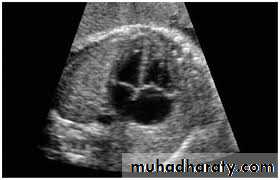

Fetal anomaly scan is performed between 18 and 20 weeks' gestation. If an abnormality is detected, detailed fetal echocardiography is performed by a paediatric cardiologist, who also checks any fetus at increased risk, e.g. where Down's syndrome is suspected, where the parents have had a previous child with heart disease or where the mother has C.H.D. The continuation of pregnancy and delivery then planned.

3-Echocardiography

The location and size of the atrial defect are readily appreciated by two-dimensional scanning . The shunt is confirmed by pulsed and color flow Doppler .